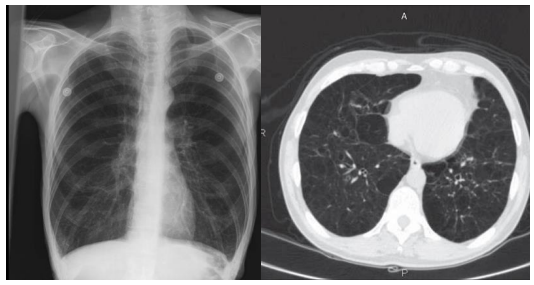

Paciente do sexo masculino, 68 anos, tabagista há 40 anos, apresenta queixa de

dispneia progressiva há 2 anos e, no momento, relata cansaço ao ir ao supermercado, localizado na esquina de sua casa. Nega febre e episódios de hemoptise. O

exame físico revela diminuição dos sons respiratórios em ambos os pulmões, com

presença de crepitações em regiões infraescapulares. Ao comparecer ao serviço

de Fisioterapia, apresentou os exames de imagem demonstrados abaixo.

Assinale a opção que MELHOR descreve os achados radiológicos e tomográficos demonstrados e a possível hipótese diagnóstica: